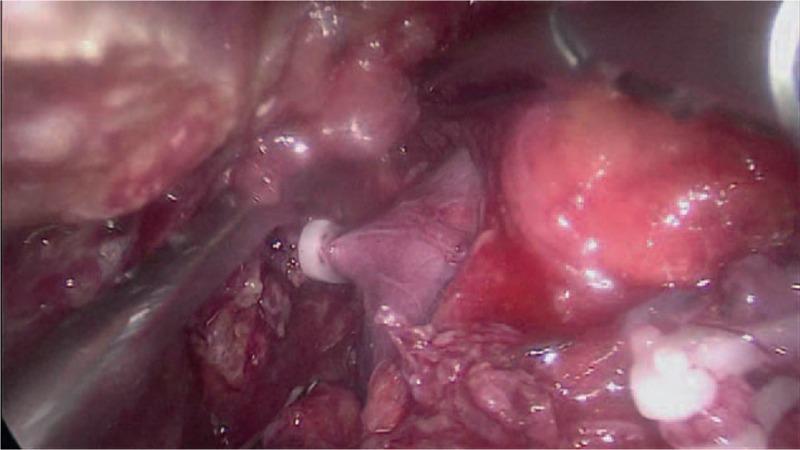

Staged hepatectomy is an important surgical method for large hepatocellular carcinoma (HCC). However, the insufficient future liver remnant (FLR) is still the major barrier in stage II hepatectomy. We herein reported a case of laparoscopic associating liver tourniquet and portal ligation combined rescue transhepatic arterial embolization (TAE) for staged hepatectomy.

Laparoscopic associating liver tourniquet and portal ligation for staged hepatectomy (ALTPS) was performed for cirrhotic HCC in stage I. To stimulate the growth of FLR, a "rescue" TAE was initiated before stage II.

Two weeks later after TAE, the FLR achieved sufficient hypertrophy and stage II surgery was successfully performed. The patient was discharged 7 days after the second stage without serious complication. During the follow-up at postoperative 6 months, the patient underwent radiofrequency ablation, because contrast-enhanced ultrasonography showed 1 cm tumor recurrence in the remnant liver.